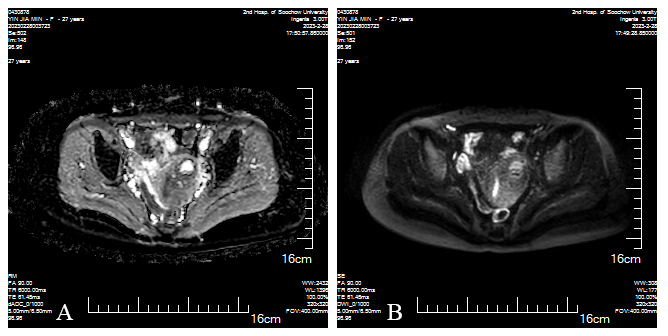

Fig. 4. March 2, dADC (D-1), DWI (D-2) showed low signal intensity on the left side of the uterus. (A) dADC and (B) DWI both confirm low signal intensity on the left side of the uterus, with fluid present within this lesion, a possibility of gestational sac rupture and bleeding is suggested.